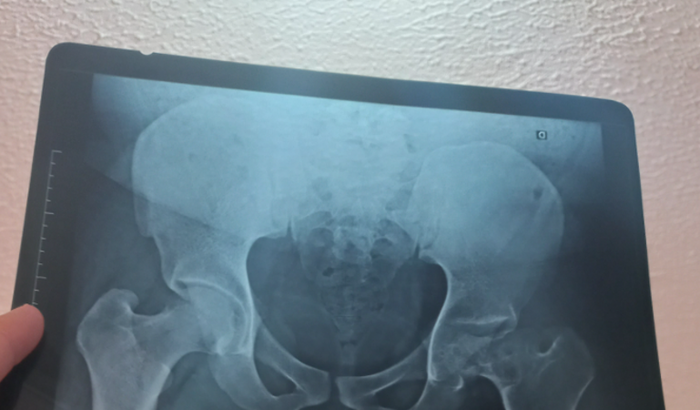

Ola me chamo aleff tenho 28 anos e venho aqui pedir sua ajuda para a realização de uma cirurgia no quadril , tenho artrose avançada , a cabeça do meu femu direito esta muito desgastada , estou com a perna esquerda menor que a direita vem atrofiando a cada dia que se passa , estou na fila do sus a muito tempo porém , vai demorar muito e o quadro de dor é muito intenso , e nao tenho mais oque fazer pois é uma cirurgia muito cara e não tenho condiçoes de realizar por isso venho aqui pedir a ajuda de voces , para melhora minha qualidade de vida , pois meu sonho é ter uma vida normal , e poder trabalhar um dia , e compatilhando com voces as fotos dos meus exames.